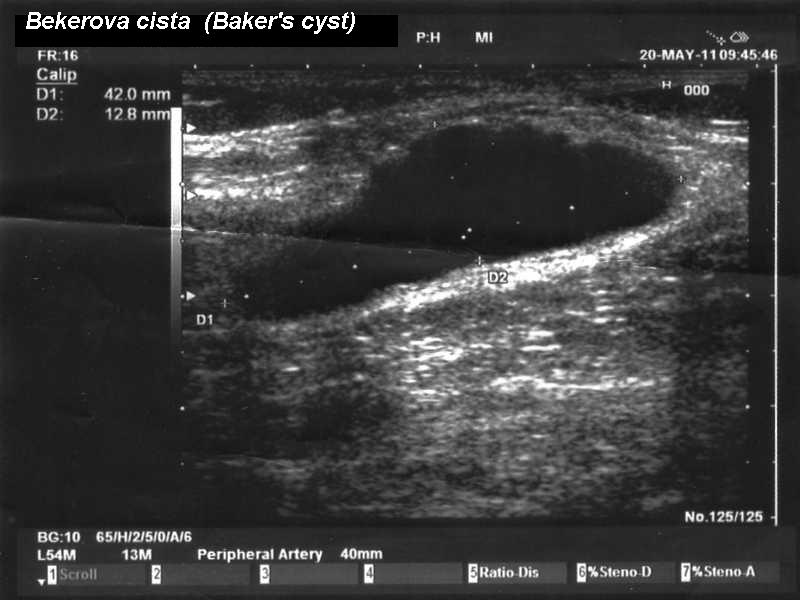

超音波可協助檢查貝克氏囊腫

如果身體檢查起來仍有疑慮,最方便的方法其實是用超音波檢查,超音波能夠輕易區分水囊與水腫的差別,在膝膕窩的肌肉層中間發現從膝關節破出去的水囊,加上有發炎性關節炎的症狀,臨床上即可懷疑是貝克氏囊腫。